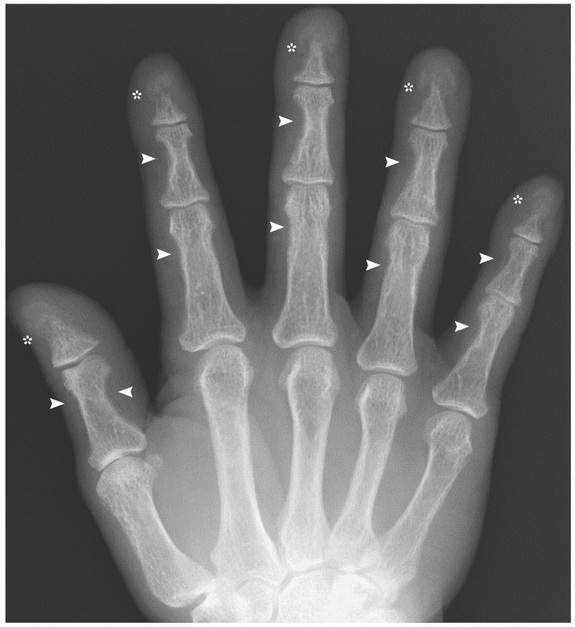

Prin urmare, oasele lui au devenit foarte fragile, iar degetele de la mâini au început să se atrofieze, să se micşoreze.

Din cauza afecţiunii, unele celule specializate distrug oasele, pentru a elibera calciu în sânge, rezultând astfel o atrofierea oaselor.

Radiografiile sunt o procedură de rutină în cazul persoanelor bănuite de hiperparatiroidism, dar boala poate fi depistată şi în urma unor teste de sânge.